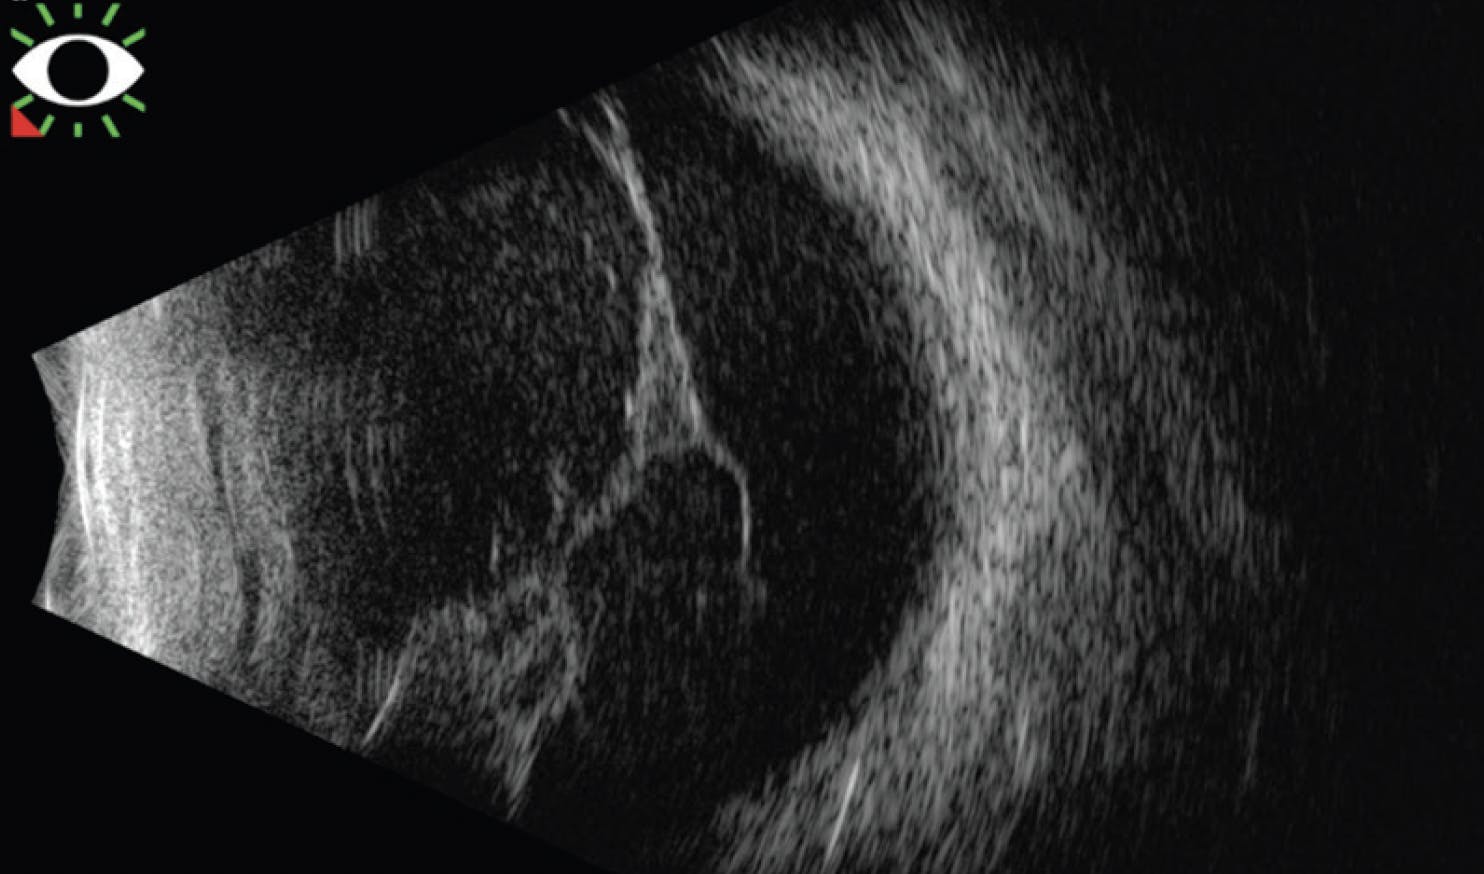

At presentation, the patient’s BCVA was light perception OS and 20/60 OD. Slit-lamp examination of the left eye showed dense vitreous hemorrhage against the posterior of the lens with no fundoscopic view. B-scan ultrasound of the left eye showed dense opacities and membranes throughout the vitreous (Figure 1). A V-shaped membrane was attached at the disc, suggestive of a funnel retinal detachment (RD).

<p>Figure 1. B-scan ultrasound of the patient's left eye showed a V-shaped membrane attached at the disc.</p>

Figure 1. B-scan ultrasound of the patient's left eye showed a V-shaped membrane attached at the disc.